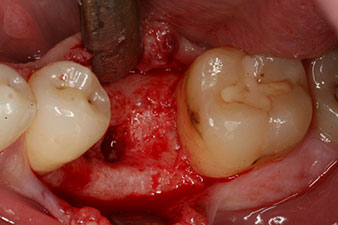

unvollständige Ossifikation

Abb. 2: Sechs Wochen später zeigt sich eine nur unvollständig ossifizierte Alveole im Bereich der mesialen Wurzel.

Sechs Wochen nach Extraktion zeigte sich jedoch nach Präparation des Mukoperiostlappens im Bereich der ehemaligen mesialen Alveole eine unvollständige Ossifikation.